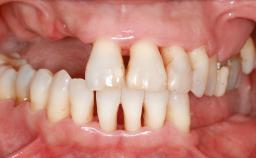

A 20-year-old woman was referred for implant therapy in 2004. Her medical history revealed no significant findings, and neither did she smoke nor take any medications. An extraoral examination revealed no abnormalities of the skin, hair or nails. The intraoral examination revealed only 11 permanent teeth clinically. These were normal in shape, size, and color. In addition, eight retained deciduous teeth (53, 62, 63, 71, 72, 73, 81, 82) were present. No abnormalities were detected during the general examination. The family history revealed that the patient’s father and two sisters were on record with similar conditions. The clinical examination revealed a thick gingival biotype. No recession of the attached gingiva was noted, but the retained deciduous teeth were mobile and unsightly. As a syndrome had not been diagnosed, the case was categorized as non-syndromic oligodontia.

Bone Volume Horizontally and vertically sufficient Horizontally deficient Deficient vertically or deficient vertically AND horizontally

Bone Volume Deficient horizontally, requiring prior grafting